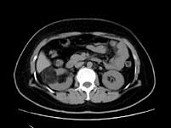

- 多项选择题男,55岁, 右腰部不适1年余,CT扫描如图所示, 下列说法正确的是 ( )

A、右肾中极可见一类圆形肿块影,肿块密度不均

B、其内见低密度脂肪影

C、其边缘清楚,与周围境界清晰

D、考虑为右肾癌

E、考虑为右肾错构瘤